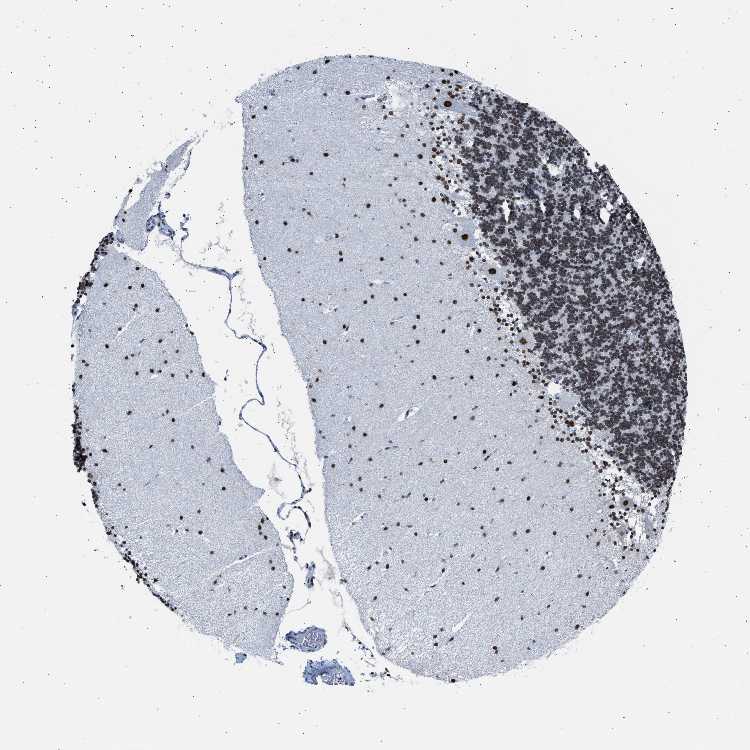

BRAIN CEREBELLUM Show tissue menu

CEREBELLUM - Expression summary

CEREBELLUM - Antibody stainingi

Antibody staining in the annotated cell types in the current human tissue is reported as not detected, low, medium, or high, based on conventional immunohistochemistry profiling in selected tissues. This score is based on the combination of the staining intensity and fraction of stained cells.

Each image is clickable and will lead to virtual microscopy that enables deeper exploration of all samples and also displays staining intensity scores, fraction scores and subcellular localization as well as patient and tissue information for each sample.

Antibody HPA019907Antibody HPA019943Antibody CAB072827

Purkinje cells HighHighMedium

Cells in granular layer LowMediumMedium

Cells in molecular layer HighHighHigh